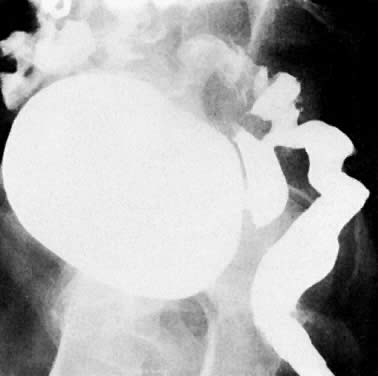

A. Plain film of abdomen. Air-filled bladder in a patient with vesicovaginal fistula. Dome of bladder is outlined with arrows. B. Cystogram. Contrast medium fills the bladder and runs onto the vaginal tampon (T) inferior to the bladder and posterior to the Foley catheter (arrow).

Barium examination of colon (lateral film). Barium flows from the rectum into the vagina and bladder. The caliber of the colon and rectum is small, and the space between the rectum and the sacrum is increased. This latter finding indicates shortening of the colon and is seen in patients with changes in the rectum caused by chronic irradiation. The lower vagina is not visualized because of coaptation of the vaginal walls after previous irradiation.